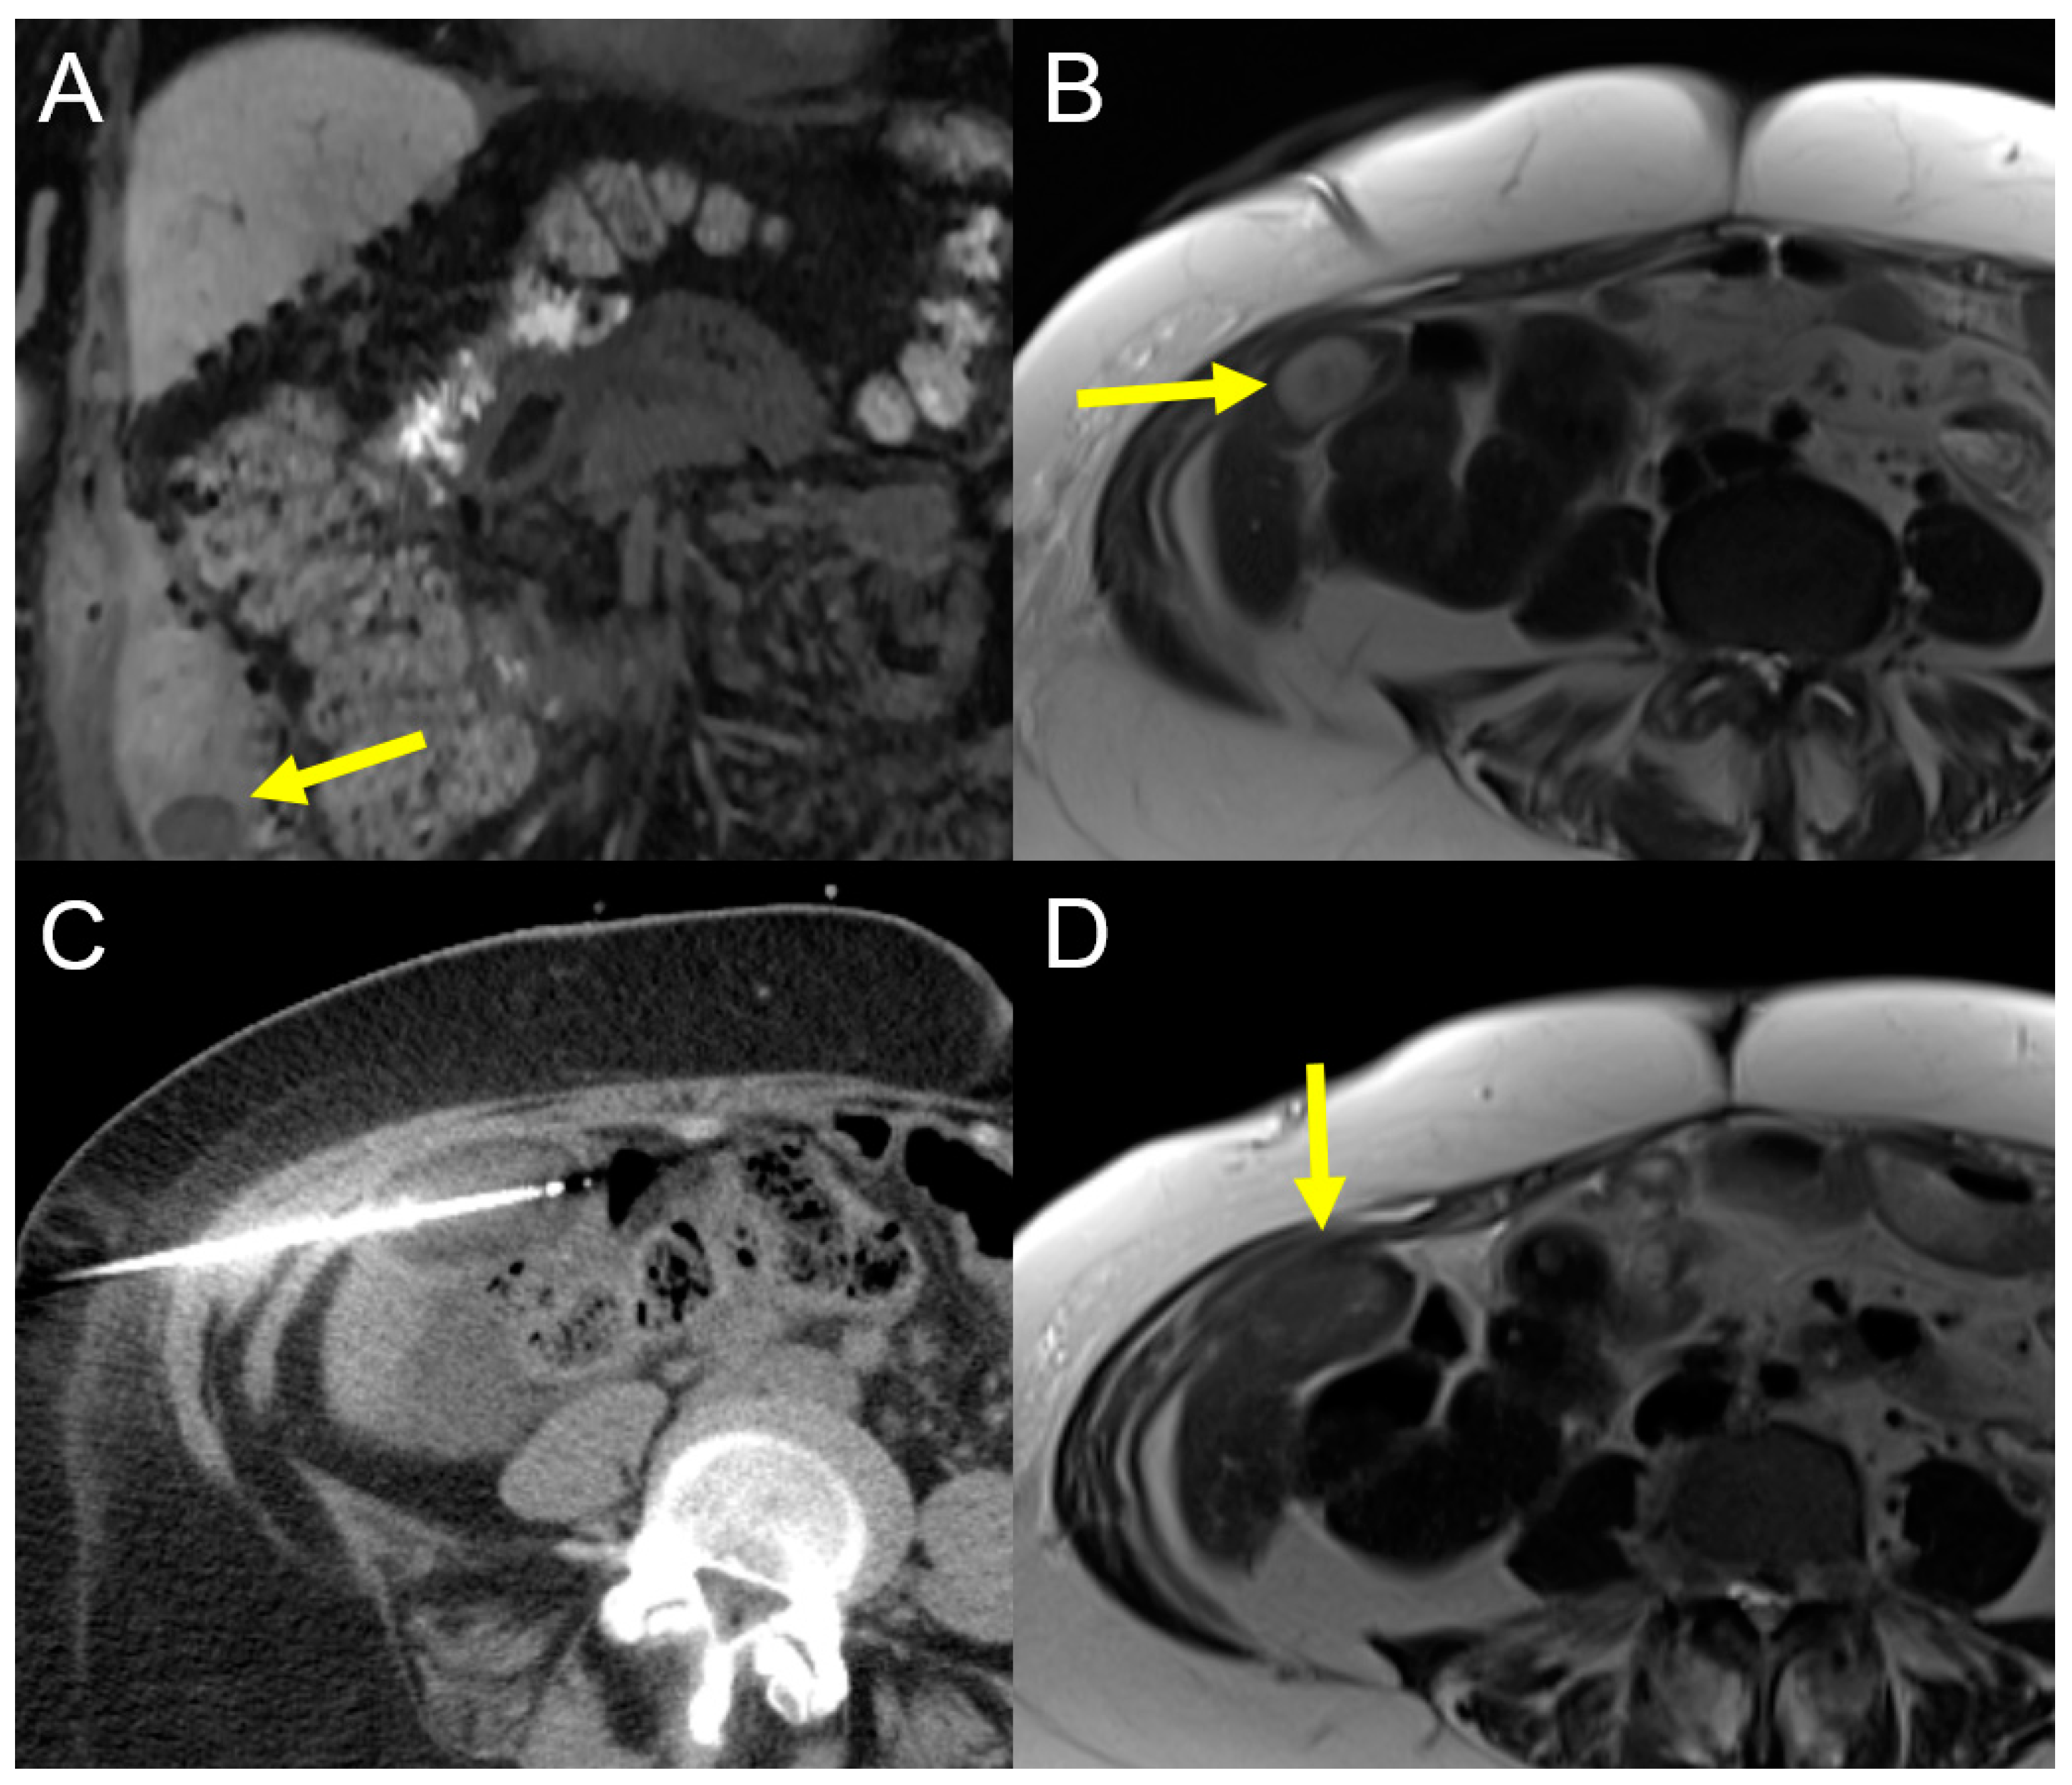

2.2.2. Irreversible Electroporation (IRE)